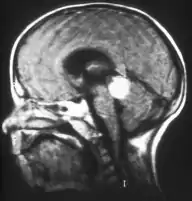

Retinoblastoma

El retinoblastoma es un tumor canceroso que se desarrolla en la retina causado por una mutación en la proteína Rb, codificada por un gen supresor tumoral denominado RB1.[1] Este tumor se presenta en mayor parte en niños pequeños y representa el 3% de los cánceres padecidos por menores de quince años. Constituye la primera causa de malignidad intra-ocular primaria en los niños y la incidencia anual estimada es de aproximadamente 4 por cada millón de niños.[2]

El retinoblastoma tiende a extenderse hacia el cerebro y la médula ósea, y más raramente se disemina por los pulmones. Estos son factores de pronóstico adverso, así como la invasión coroidal y a través del nervio óptico.[1]